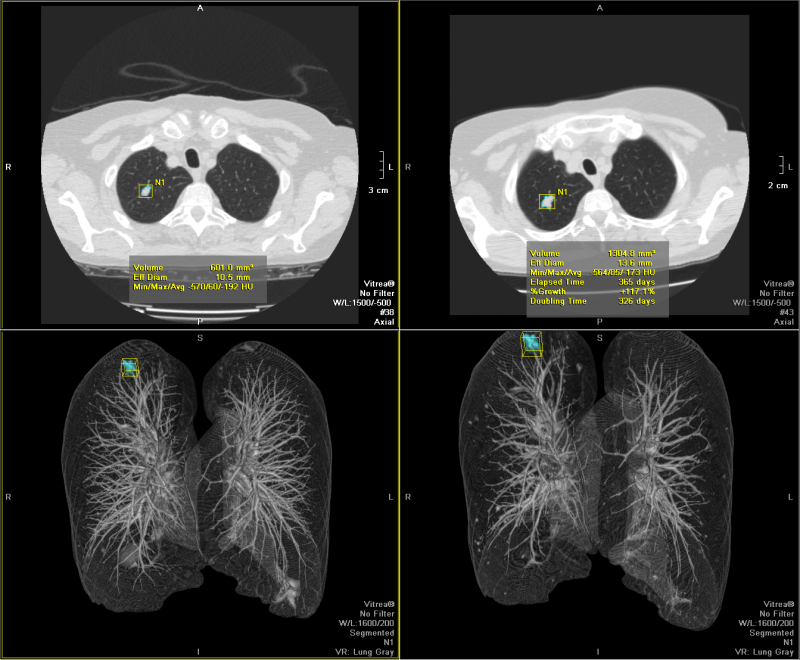

Vitrea三維影像后處理軟件產(chǎn)品說明:

VitreaTM 產(chǎn)品為醫(yī)師提供處理分析2D, 3D和4D醫(yī)學(xué)影像的全套工具, 同時(shí)支持多種 設(shè)備 - CT, MR, XA, PET, US, SPECT. 特別在心臟科, 神經(jīng)科, 腫瘤科與介入治療方面 提供了豐富而有針對(duì)性的應(yīng)用, 為醫(yī)療專家在手術(shù)計(jì)劃與救治病患時(shí)提供更多幫助.